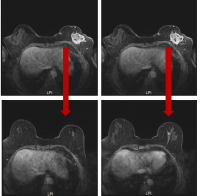

乳腺癌新辅助治疗技术

提交科室:

乳腺外科

适用的癌种:

乳腺癌